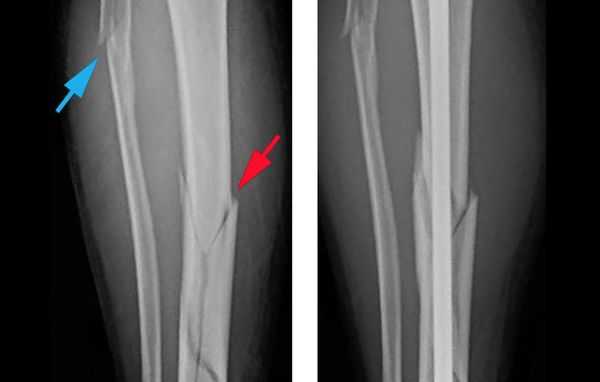

КТ коленного сустава и голени. Оскольчатый перелом большеберцовой кости в верхней трети диафиза (красная стрелка), перелом головки малоберцовой кости (синяя стрелка), перелом латерального мыщелка большеберцовой кости (зеленая стрелка).